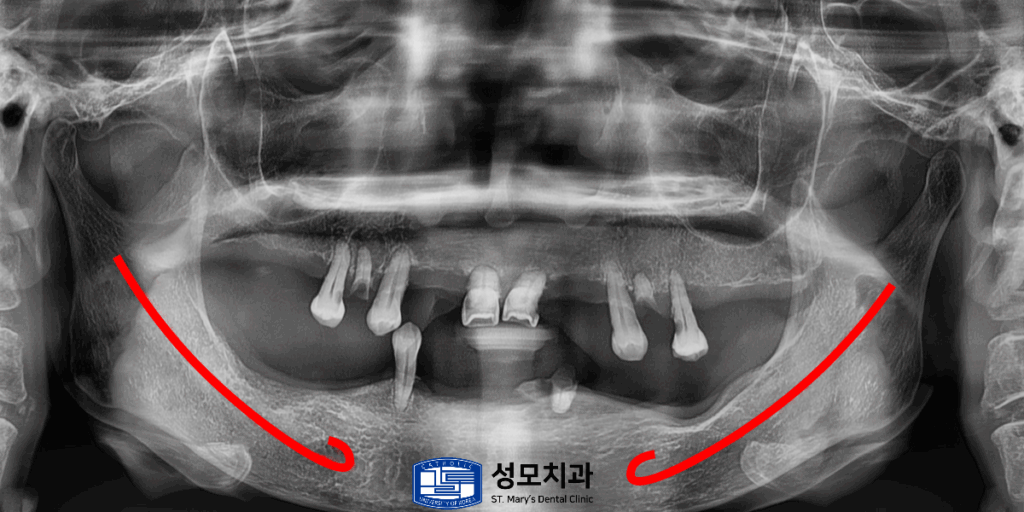

낮아진 치조골의 높이로 인해서

아래턱에 길게 지나가는 큰 신경 중 하나인

하치조 신경(빨간색)까지의 치조골 높이가

매우 부족한 상태였습니다.